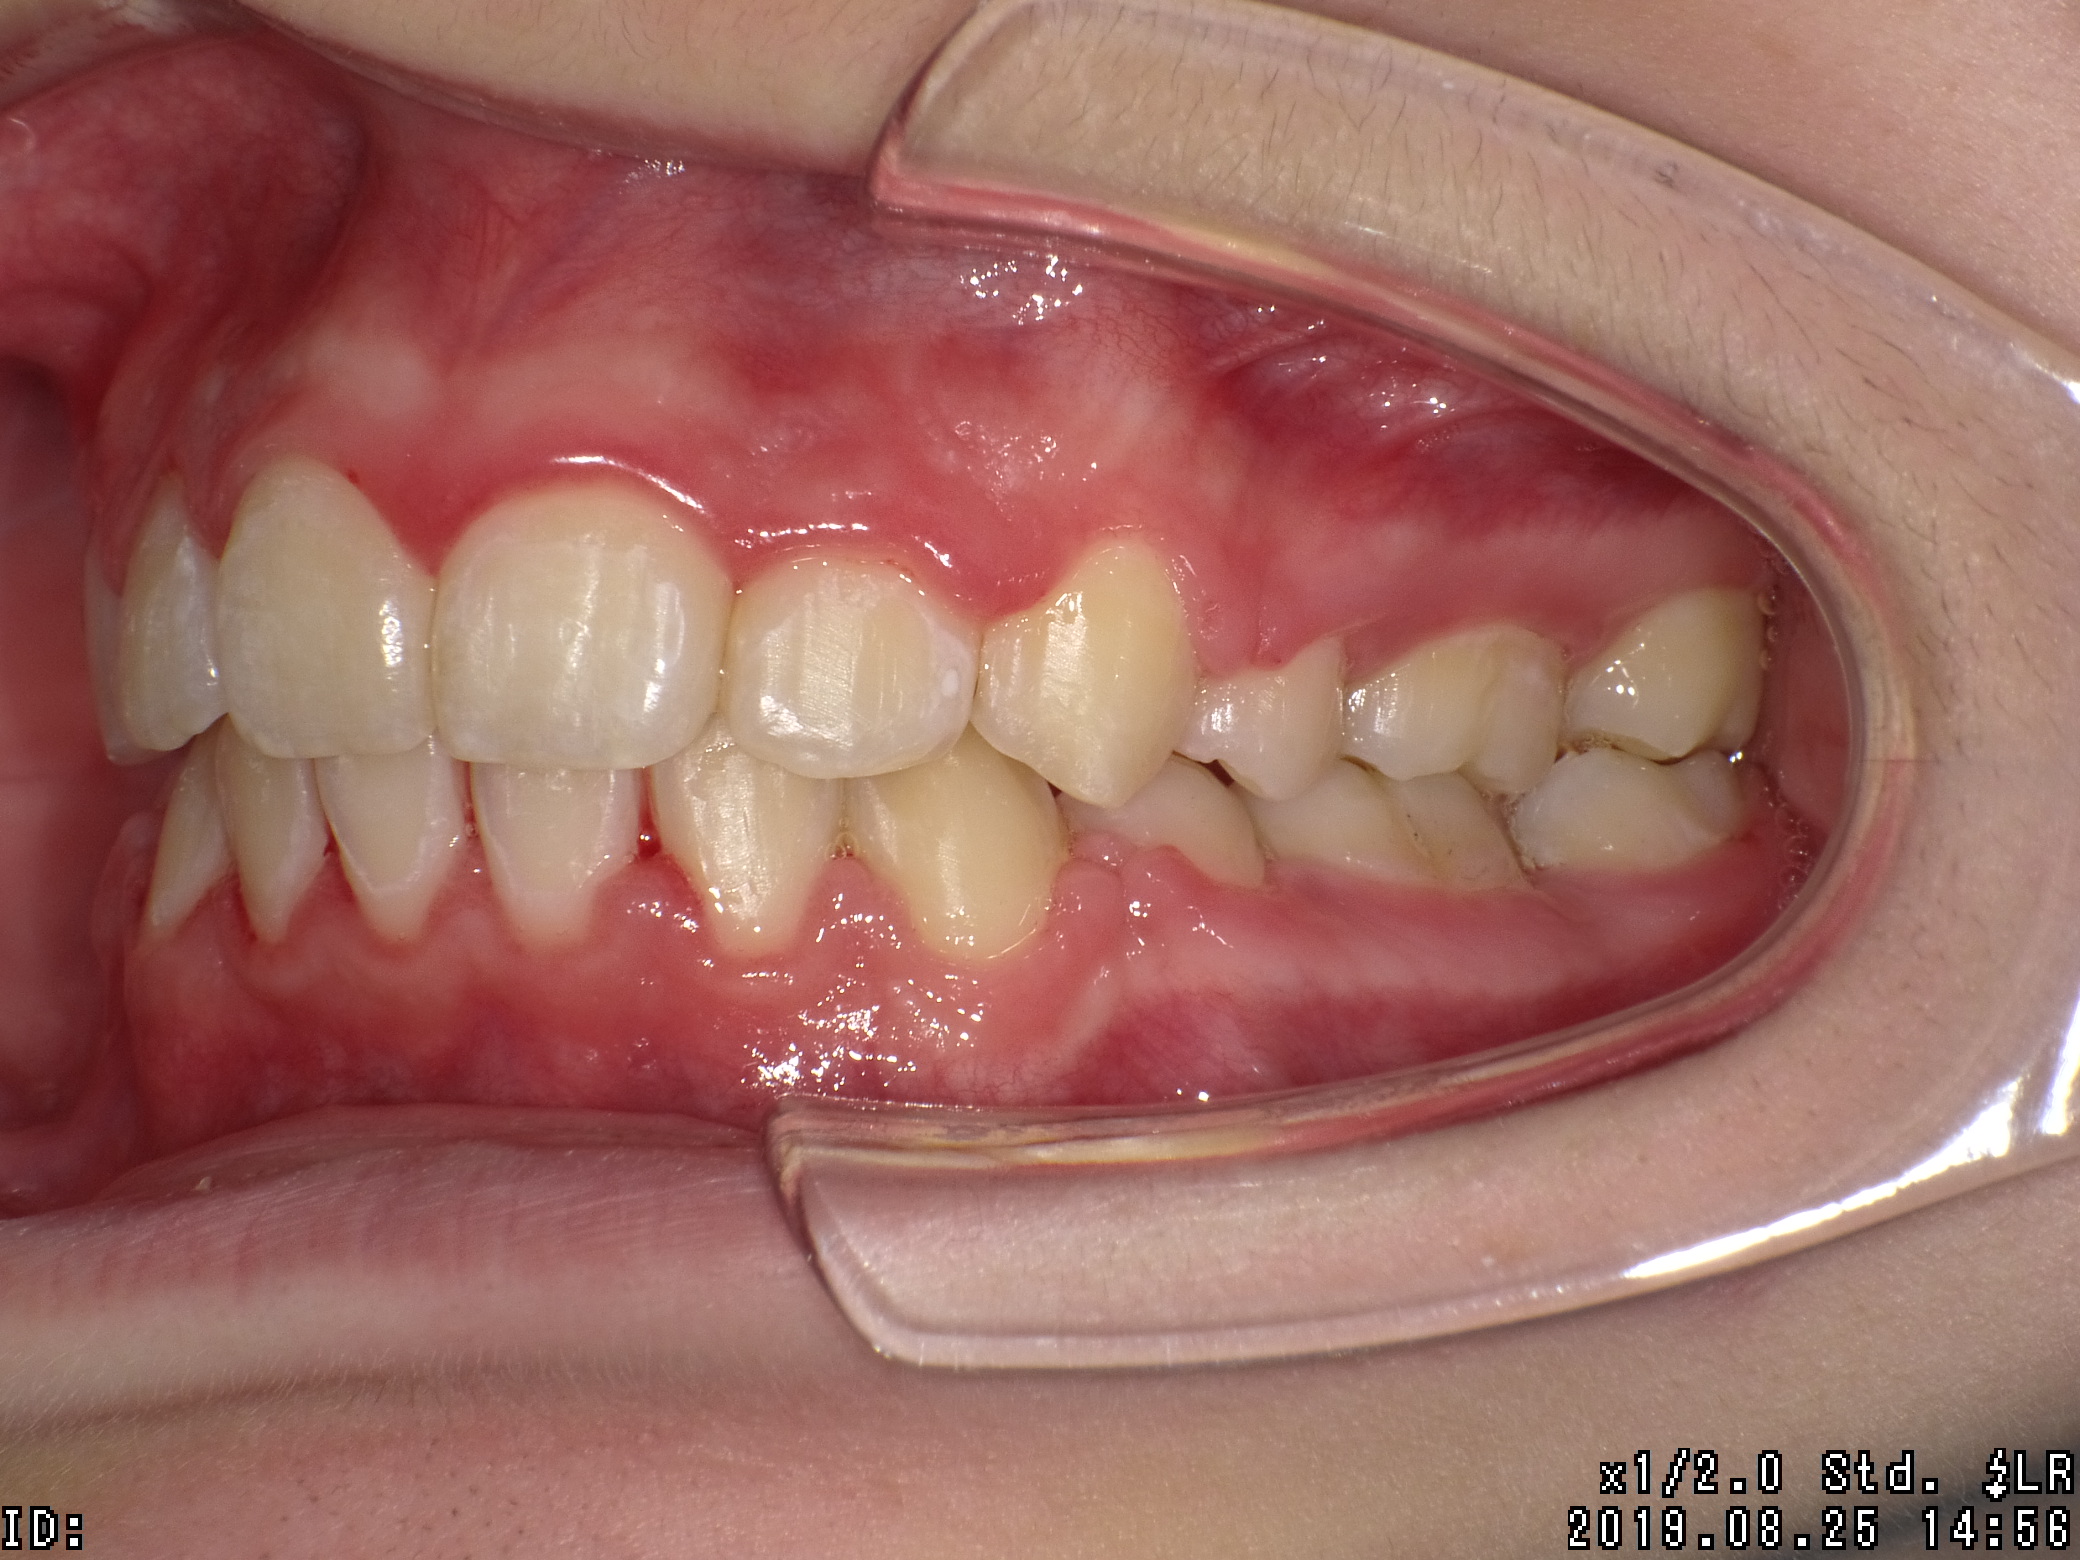

| 治療期間 | 2017年04月 〜2019年08月 |

|---|---|

| 治療費用 | 約700,000円 |

| 抜歯有無 | 抜歯有り |

| 矯正箇所 | 上顎・下顎 |

| 治療のリスク | 治療の過程で使用する針金やゴムにより、違和感や不快感を感じたり、口内炎になることがあります。 |